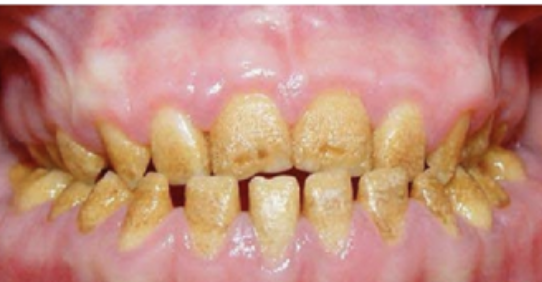

Wat is ectodermale dysplasie?

Bij ectodermale dysplasie bestaat uit hypo- of aplasie van ectodermale structuren, zoals haar, gebitselementen en oppervlakkige klieren. In de meeste gevallen is de overerving X-gebonden recessief. Persisterende koorts op kinderleeftijd wordt veroorzaakt door een inadequate warmteregulatie en afwezigheid van zweetproductie. De huid is dun en droog. De patiënten hebben fijn, dun blond haar maar de nagels zijn relatief normaal. De functie van de speeksel-, traan- en slijmklieren is vaak verminderd en de gebitselementen zijn niet gevormd of kegelvormig en klein.

Omschrijf een afwijking van de tandvorm? (Ontwikkelingsstoornis van gebitselementen)

Dit noem je ectodermale dysplasie. Dit is te zien aan afwijkingen aan de haren, de huid is droog en dun, de elementen zijn klein/kegelvorming of zijn in het geheel niet aanwezig. Bij anodontie zijn er geen enkele tanden aanwezig. Bij oligodontie zijn er meerdere (6 of meer) elementen afwezig maar niet allemaal.